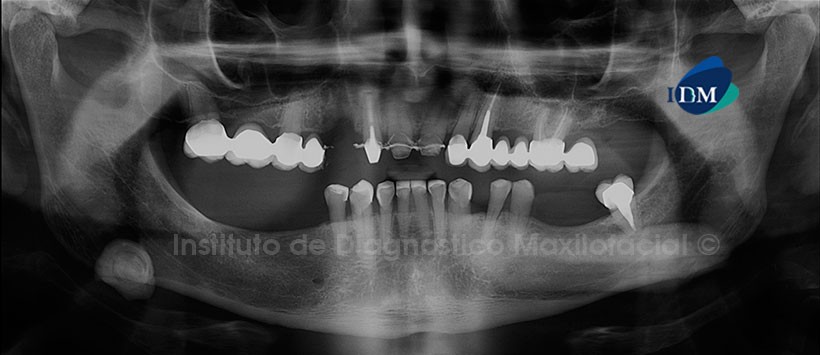

Paciente de 60 años de edad es referido al Instituto de Diagnostico maxilofacial (IDM) por evaluación para la colocación de implantes.

A la evaluación de la radiografía panorámica, se observa la mineralización de ambos proceso estilohiodeos del tipo segmentada, neumatización alveolar de ambos senos maxilares, edéntulo parcial bimaxilar, múltiples coronas protésicas siendo lo más resaltante la presencia de una imagen radiolúcida de limites definidos y de densidad de cálcica proyectada a nivel de la escotadura antegonial de lado derecho. (Figura 1)